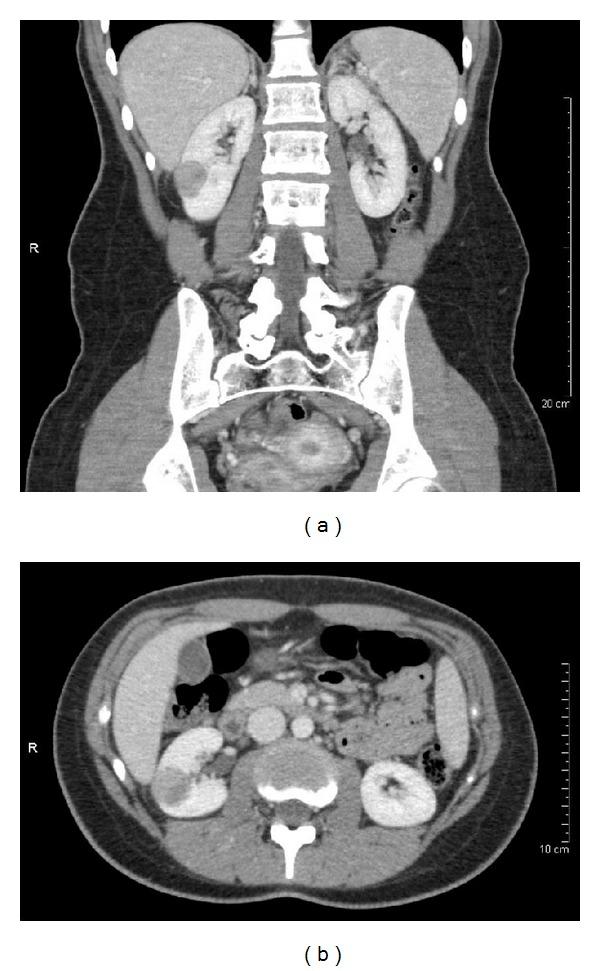

Thyroid-like follicular carcinoma of the kidney (TLFCK) is a rare histological variant of renal cell carcinoma not currently included in the World Health Organization classification of renal tumors. Only 24 previous cases of TLFCK have been reported to date. We report a case of TLFCK in a 19-year-old woman with history of pediatric acute lymphoblastic leukemia. This patient is the youngest with TLFCK to be reported to date and the first with history of lymphoblastic leukemia. The development of TLFCK in a young patient with history of lymphoblastic leukemia is interesting and suggests that genes involved in leukemogenesis may also be important for TLFCK pathogenesis. Recognition of TLFCK is important to distinguish it from other conditions that show thyroid-like features, as a misdiagnosis can result in adverse patient care.

肾甲状腺样滤泡癌(TLFCK)是肾细胞癌一种罕见的组织学变异型,目前未被纳入世界卫生组织肾肿瘤分类中。迄今为止,仅报道过24例TLFCK病例。我们报告了1例19岁患有儿童急性淋巴细胞白血病病史的女性TLFCK病例。该患者是迄今为止报道的最年轻的TLFCK患者,也是首例有淋巴细胞白血病病史的患者。一名有淋巴细胞白血病病史的年轻患者发生TLFCK很有意思,提示参与白血病发生的基因可能对TLFCK的发病机制也很重要。认识TLFCK对于将其与其他具有甲状腺样特征的疾病相鉴别很重要,因为误诊可能导致对患者不利的治疗。